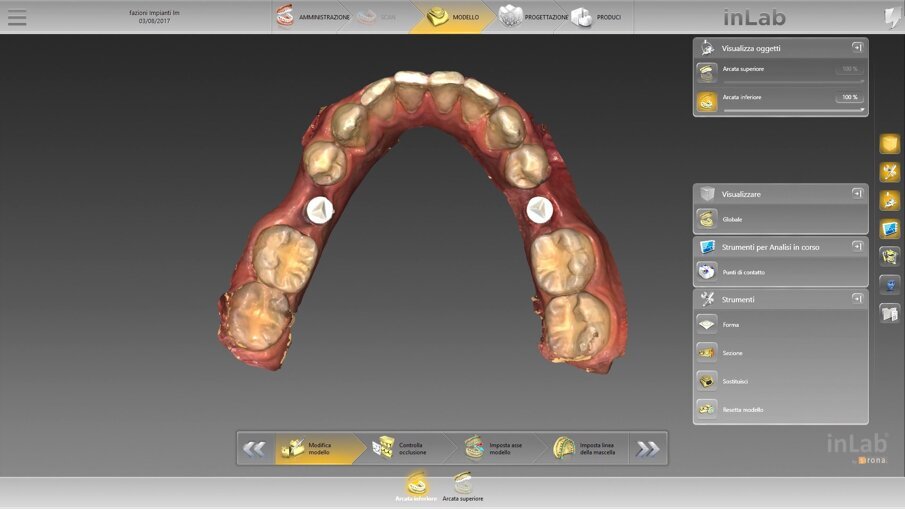

Fig. 10_Il rendering con il software Dentsply Sirona inLab.